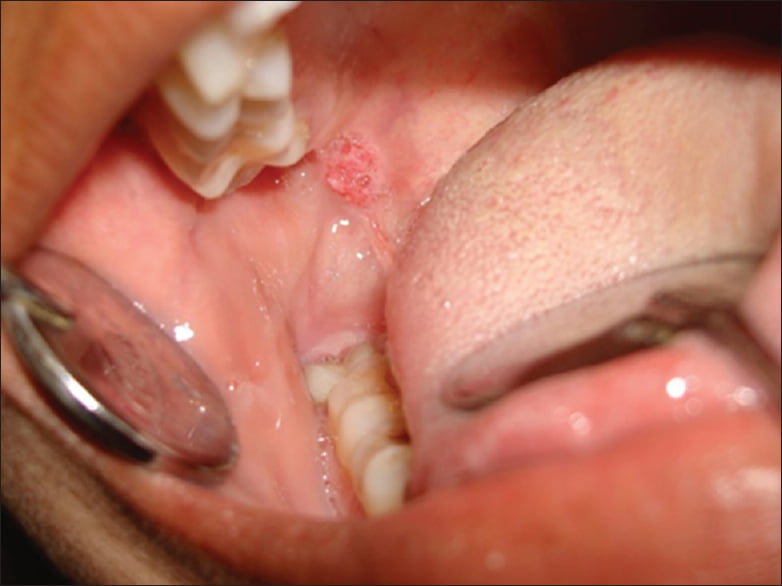

The initial symptoms of ACC will depend on the location of the tumor. The early lesions of the salivary glands can appear as painless, usually slow – growing masses underneath the normal lining of the mouth or skin of the face. There are many salivary glands under the mucosal lining of the mouth, throat and sinuses and the lumps in these locations could be from this type of tumor. There can be other symptoms of ACC [2,3], such as

- The lump on the palate, under the tongue, or in the bottom of the mouth

- An abnormal area on the lining of the mouth